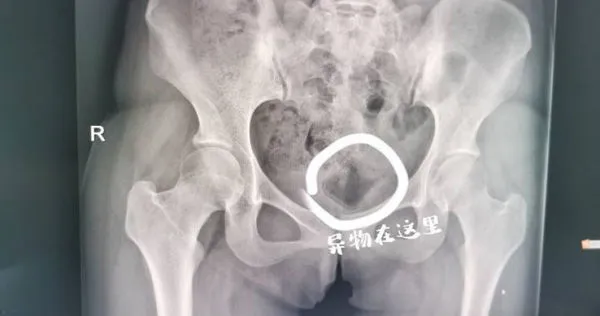

雖然閨房情趣能增進情侶或夫妻間的感情,但若沒有拿捏好分寸,恐怕只會帶來反效果。大陸浙江省杭州市一名女大生近日到醫院求診,害羞地喊著下體疼痛;經醫師詢問,才得知原來患者和男友追求刺激,竟把異物塞進下體,事後怎麼拿也拿不出來,但又不好意思就醫,直到痛到無法走路,才到婦產科尋求協助。

《錢江晚報》報導,19歲的小楊(化名)是名大學生,不久前交了男友,2人為了尋求刺激,竟將異物塞進下體。由於缺乏醫學常識,再加上心裡窘迫,小楊覺得這件事難以啟齒,一直沒到醫院檢查,也沒有告訴其他人,直到1個月後下體開始飄出異味,且疼痛難耐,才在朋友陪同下到杭州市西溪醫院婦產科就診。

醫生檢查發現,小楊的陰道深處的確有異物,該物體光滑且無著力點,憑普通醫療器械工具無法取出。高建松醫師表示,雖然異物在體內停留的時間長,所幸位置不算深,於是在超音波的引導下,經過多次探查,最後終於用手術鉗取出了小楊體內的異物,原來是個長5公分寬3公分、類似化妝品蓋子的東西。